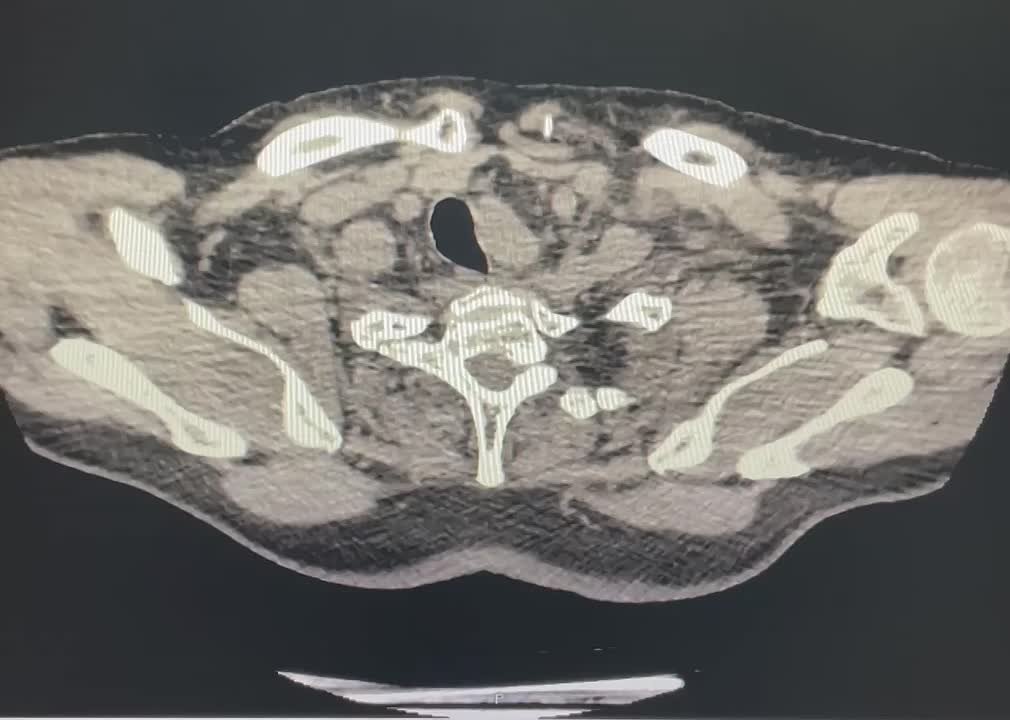

Врачи выявили опасную патологию — расширение и истончение участка главного сосуда организма — дуги аорты. Это могло привести к разрыву и кровотечению. Кроме того, у пенсионера остановилось сердце и дыхание.